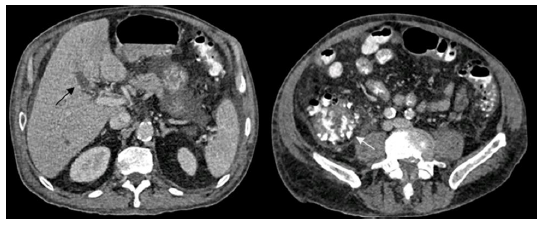

Los hemocultivos resultaron ser positivos para Escherichia coli resistente a ampicilina y Streptococcus dysgalactiae. Se decidió ajustar el antibiótico a piperacilina/tazobactam y realizar tomografía de abdomen simple y contrastada que evidenció hígado con parénquima hipodenso y ausencia de llenado parcial en territorio de la porta hepática y su rama izquierda por trombos (figura 2). Además, en las asas intestinales se observaba inflamación en la válvula ileocecal y múltiples divertículos en todo el colon; configurando un diagnóstico de diverticulitis aguda y trombosis séptica portal asociada, también conocida como pileflebitis.